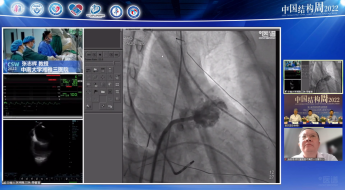

广东省人民医院罗建方教授团队带来一例二尖瓣机械瓣置换术后TAVR手术。由于该患者也存在三尖瓣关闭不全问题,但考虑到右心衰不严重,则优先处理主动脉狭窄问题。术后患者血流动力学稳定,舒张压64mmHg,无瓣周瘘问题。

手术策略:全身麻醉、右股入路、无预扩张、23mm或26mm可回收输送系统。